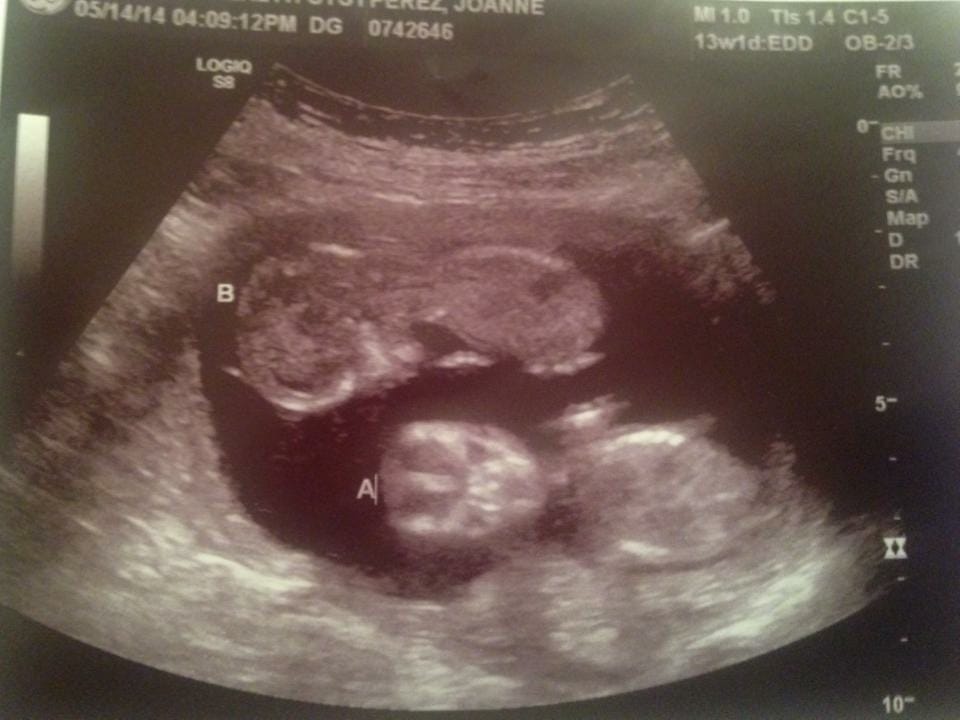

- Ultrasound Photos at 13 Weeks Pregnant With Twin

Ultrasound Photos at 13 Weeks Pregnant With Twin